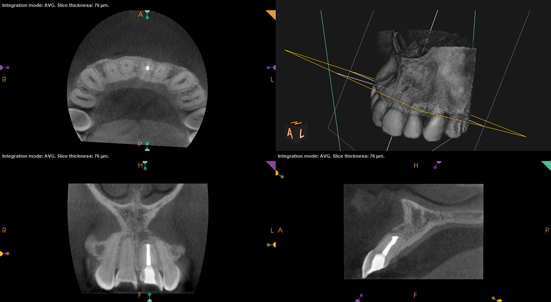

(10.) Posttreatment radiograph and cone-beam computed tomography (CBCT) scan following nonsurgical root canal re-treatment that resulted in incomplete resolution of symptoms in response to percussion and palpation.

Figure 10

(11.) Posttreatment radiograph and cone-beam computed tomography (CBCT) scan following nonsurgical root canal re-treatment that resulted in incomplete resolution of symptoms in response to percussion and palpation.

Figure 11